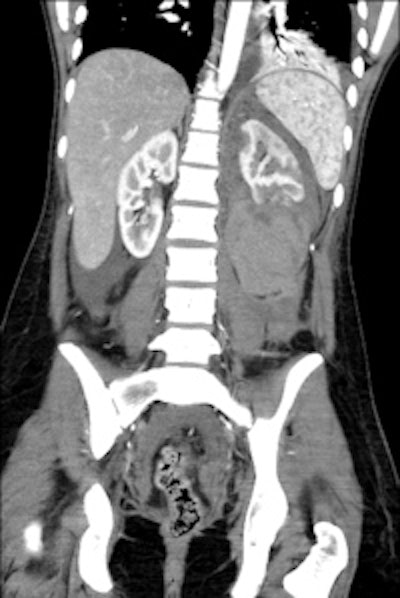

Left: A 33-year-old male with spina bifida. Reconstructed coronal maximum intensity projection CT image shows bilateral staghorn calculi and horse-shoe kidney. Right: A 37-year-old male with spina bifida. 3D reconstruction demonstrates the logistical difficulties with imaging, treatment, and management due to gross bony deformities. Images courtesy of Dr. Sanjay Agarwal.Currently, there is ongoing research for management of neurogenic bladder dysfunction. In the short term, simple things such as safer tube drainage using biofilm blocking and dispersive agents and closed tube drainage systems may help with reducing infection rates. More complex research is being conducted from multiple angles -- for example, application of gene therapy (use of herpes simplex virus-derived vectors, etc.), development of newer medication (afferent pathway drugs) and tissue regeneration (tissue-engineered autologous augmentation cystoplasty). All will have roles to play in future management of these patients, making this a very exciting time, Agarwal pointed out.